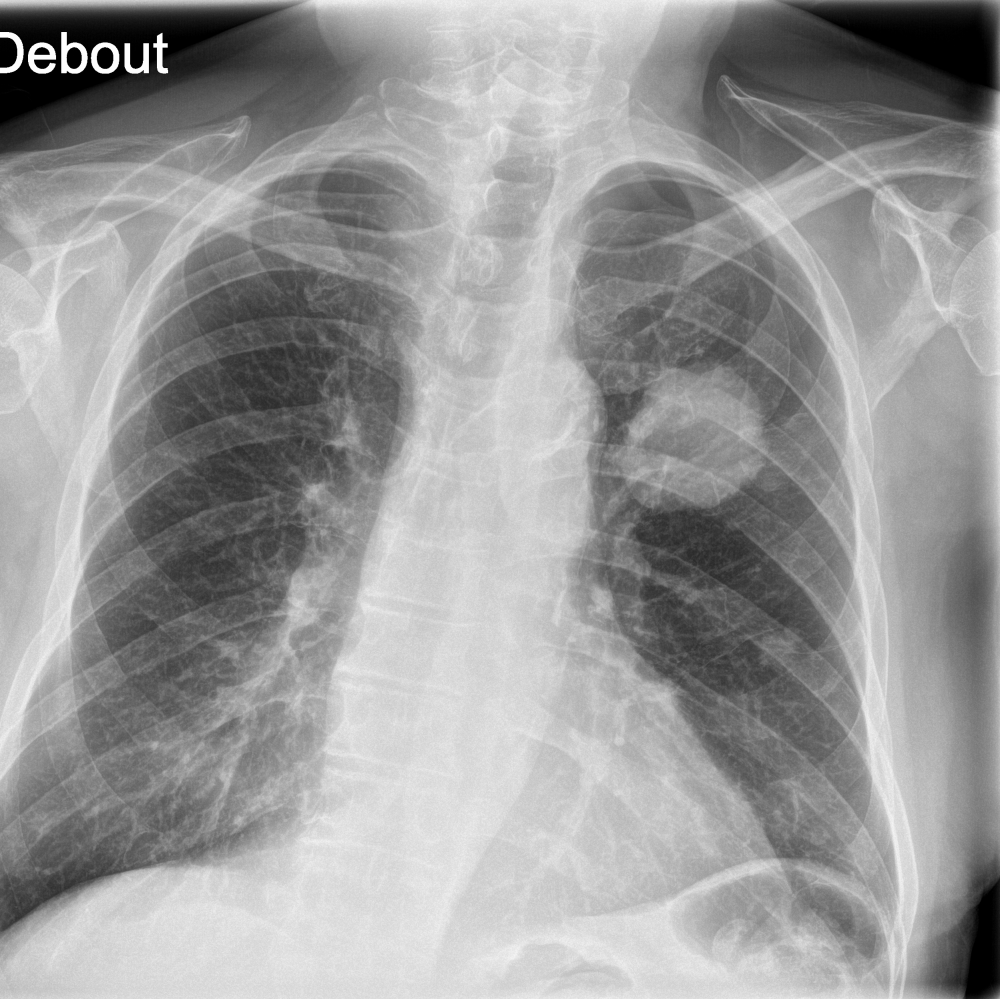

Indication

An 80-year-old male with a previously normal chest X-ray presents for CT evaluation 9 months later, which reveals findings suggestive of lung cancer.

Results

ChestView detected the mediastinal mass on the initial X-ray.